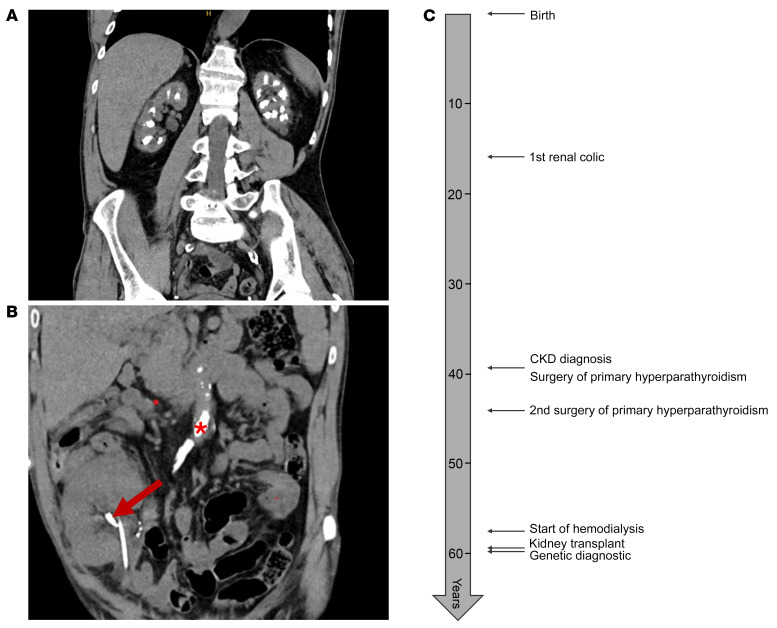

"Clinical evidence for independent regulation of vitamin D by intestinal CYP24A1" Sandrine Lemoine, et al- JCI 2025